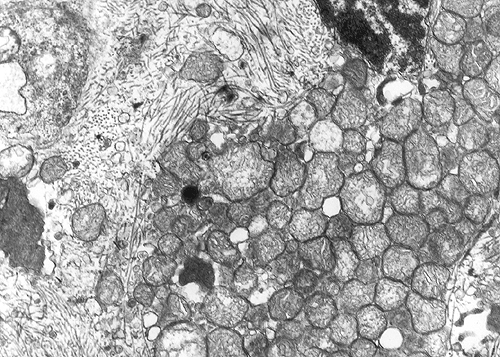

Electron microscopy: A substantial amount of mitochondria is present in the cytoplasm (Panel E and F). Admixed with the mitochondria are some small vesicles that typically have a dense core surrounded by a thin halo (Arrow in Panel E and F) and these are scare neuroendocrine (dense core) granules. Many of the mitochondria are also swollen (Panel G) and this feature may be a genuine feature or a result of mild artifact due to slight delay in fixation.

Under the electron microscope, the cytoplasm of oncocytoma is filled with mitochondria. A sparse number of neurosecretory granules (dense core granules) can also be seen. Both features are illustrated in our case.